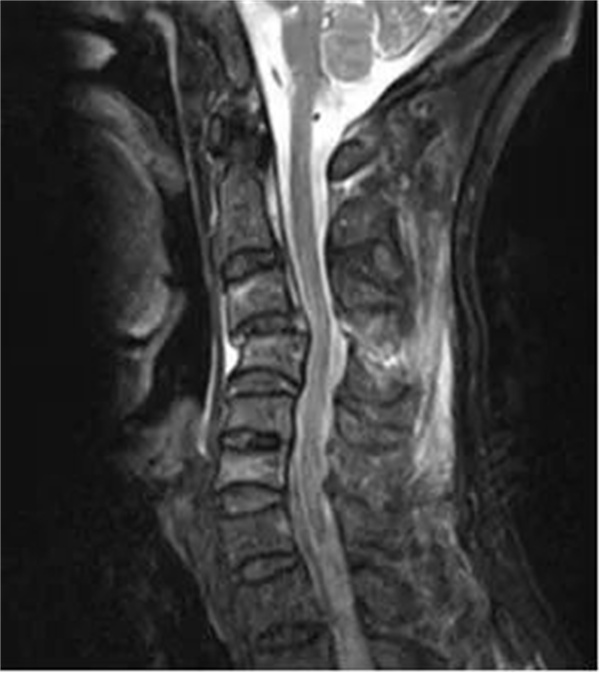

近日,61岁的刘伯(化名),不慎从高处坠落,当即颈部剧痛,颈部活动严重受限,合并有四肢肌力减退,其中右上肢不能抬起,双手活动无力。在当地医院CT检查提示存在颈椎骨折脱位,因伤情急重复杂,刘伯及家属慕名立刻转来萍乡市第二人民医院脊柱外科就医。

术前

市二医院脊柱外科完善相关检查之后诊断为“颈椎骨折脱位合并脊髓损伤,不完全性瘫痪”。该患者第3颈椎骨折伴有双侧关节突脱位交锁,颈椎移位直接压迫脊髓导致不完全性瘫痪,属于颈椎损伤中的严重类型。因颈椎骨折脱位的节段高,如不能迅速复位解除颈髓的压迫并恢复颈椎稳定性,则会导致患者瘫痪症状加重甚至危及生命。